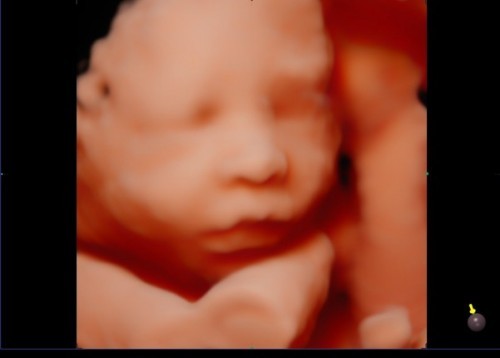

อีก4วันคุณหมอจะซาวด์ให้เห็นหน้าลูกแบบนี้เลยค่ะตื่นเต้นมากอยากเห็นหน้าลูกแล้ว

ซาวส์แบบนี้แม่ซาวส์ที่ไหนคะเสียค่าซาวส์เท่าไหร่อยากเห็นหน้าลูกค่ะ

ซาวส์ ตอนกี่วีค ค่ะ ถึงจะเห็นชัดแบบนี้

ไม่ทราบว่าซาวน์4มิติ กี่สัปดาห์คะ ค่าใช้จ่ายเท่าไหร่คะ

ซาวด์ที่ รักษ์นรีคลินิก ค่ะ 26 สัปดาห์ขึ้นไป จ่ายไป 2000 ค่ะคุณแม่ ทางคุณหมอจะให้ทั้งรูปและวิดิโอ หมอจะถ่ายจนกว่าจะเห็นหน้าเด็กชัดๆค่ะ 🥰